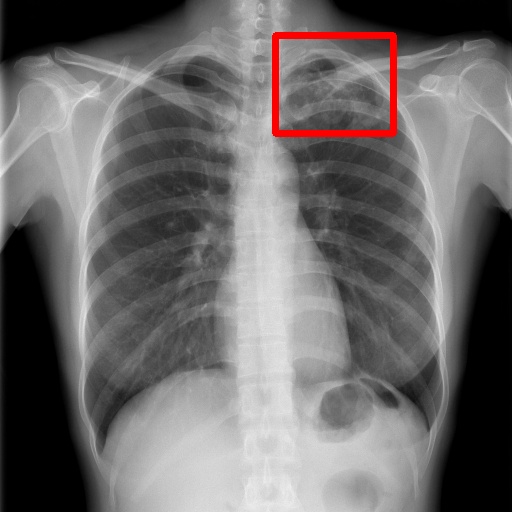

6.4 Visualization

To gain insights into the learning process of deep neural networks on CXR images, we visualize the feature map of SymFormer w/ RetinaNet at a scale of . To achieve this, we employ principal component analysis (PCA) to reduce the channels of the feature map to a single channel. The resulting single-channel map is then converted into a heat map for visualization purposes. The visualization of the learned features, along with the corresponding detection results, are presented in Fig. 6. Upon analysis, we observe that the visualization of healthy cases exhibits irregular feature patterns, indicating the absence of significant abnormalities. In contrast, the visualization of sick but non-TB cases displayed some discernible highlights, potentially representing the presence of lesions. For TB cases, the highlights in the visualization map align well with the annotated TB infection areas, thereby indicating the effectiveness of the proposed SymFormer in learning deep features for TB area detection. Furthermore, in Fig. 7, we offer qualitative comparisons between the proposed SymFormer and the baseline models for TB infection area detection. As evident, SymFormer consistently delivers superior qualitative detection results.